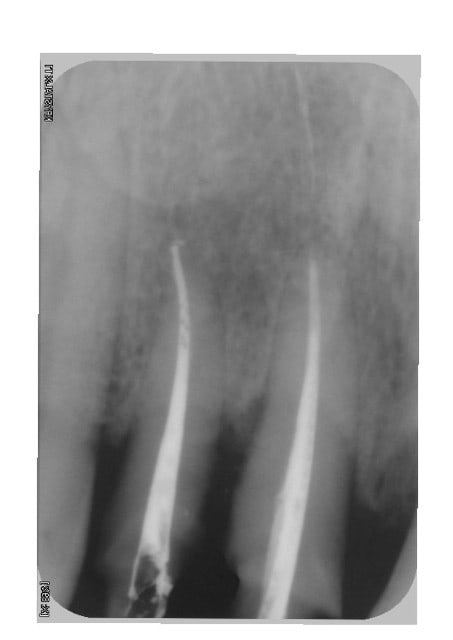

dévitalisation retraitement de 22/21/11/12 et 26 remplacement des amalgames par du composite et tout le reste dents vivantes.

le patient ne fume plus depuis 21 jours sur les dernières photos, mais je ne sais pas si mon plan de traitement suffira à lui redonner une gencive correcte.